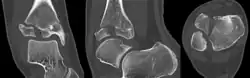

Tillaux fracture

A Tillaux fracture is a Salter–Harris type III fracture through the anterolateral aspect of the distal tibial epiphysis.[1] It occurs in older adolescents between the ages of 12 and 15 when the medial epiphysis had closed but before the lateral side has done so,[2] due to an avulsion of the anterior inferior tibiofibular ligament, at the opposite end to a Wagstaffe-Le Fort avulsion fracture

| X-ray of a Tillaux fracture in an 11 year old female | |